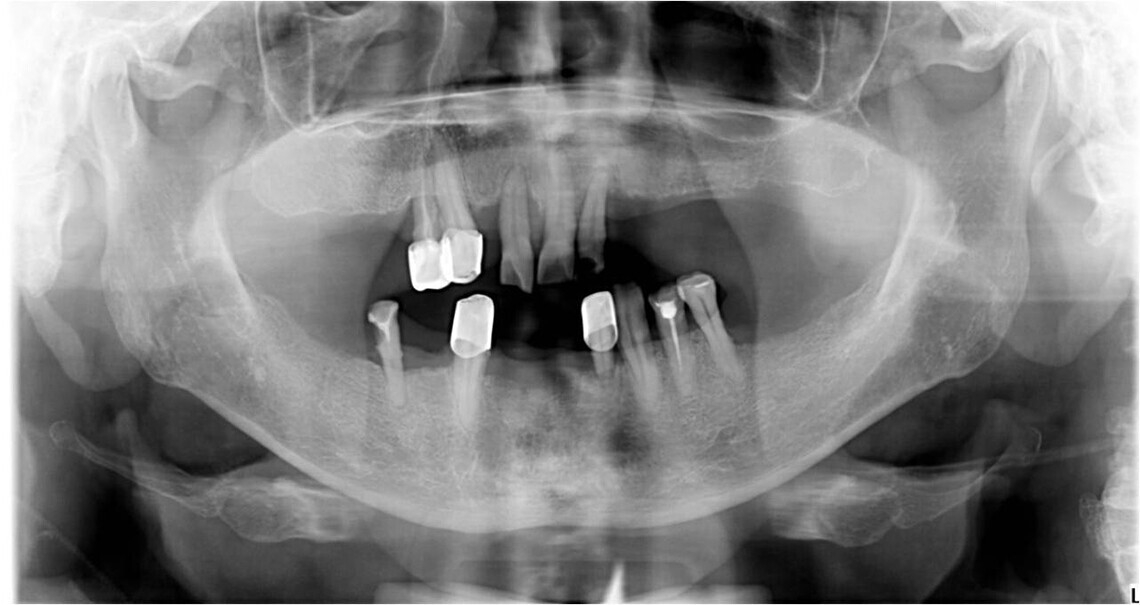

- Подготовка челюстей: лечение зубов и десен, удаление мертвых зубов или установка имплантатов.

- Препарирование зубов под коронки.